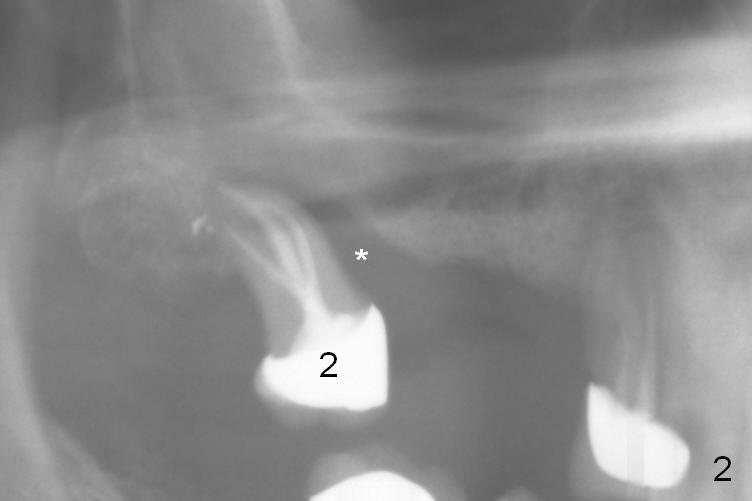

A 71-year-old man had poor dentition 4 years ago (Fig.1). Since then severe bone loss has occurred at the teeth #2 (Fig.2 *), 30 and 31 (Fig.3 *). An original plan is to place implants at #29 and 31 and fabricate a 3-unit bridge. Since the bone height at #31 is limited, primary stability may be questionable. It is advantageous to place 3 implants at #29-31. As the bone loss is severe and the sockets at #30 and 31 are long (Clindamycin), a fairly long portion of the implants at #30 and 31 will be not covered by the native bone (Fig.4 yellow line: 6-7 mm, bare) in spite of using 6 mm cuff (pink) of 7 mm abutments (brown). Use initial drill from DIO Sinus Master Kit with 5 mm stopper at #31 (green line), followed by insertion of a marked parallel pin. Use regular drills with stoppers of 10 and 8 mm at #29 and 30 (green line). Continue osteotomy at #31 with round drills (2.8 and 3.6 mm) with shorter stopper to avoid injury to the underlying Inferior Alveolar Canal (red dashed line). Pack allograft well around the implants at #30 and 31 before placing abutments to reduce periimplantitis and insert collagen plug around the abutments to prevent loss of the bone graft underneath. The last method to secure the bone graft is a retentive, splinted provisional.

It appears that the endo perio disease is more severe than 6 months ago (Fig.5,6). Prepare PRF and Extra Wide implants as well.